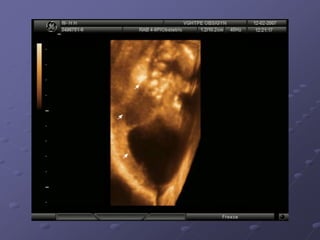

Ultrasound: An advanced ultrasound can also detect

signs of spina bifida.

Ultrasound: An advancedultrasound can also detect signs of spina bifida. Amniocentesis An analysis indicates the level of AFP present in the amniotic fluid. A small amount of AFP is normally found in amniotic fluid. when an open neural tube defect is present, the amniotic fluid contains an elevated amount of AFP because the skin surrounding the baby's spine is gone and AFP leaks into the amniotic sac. MRI